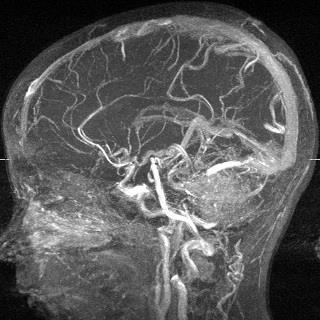

Ангіографія судин головного мозку

Ангіографічне дослідження судин мозку використовується при діагностиці та лікуванні інсультів, пухлин і аневризм, стенозу сонних артерій. Церебральна ангіографія допомагає своєчасно визначити наявність і локалізацію уражень, підібрати оптимальний спосіб лікування.